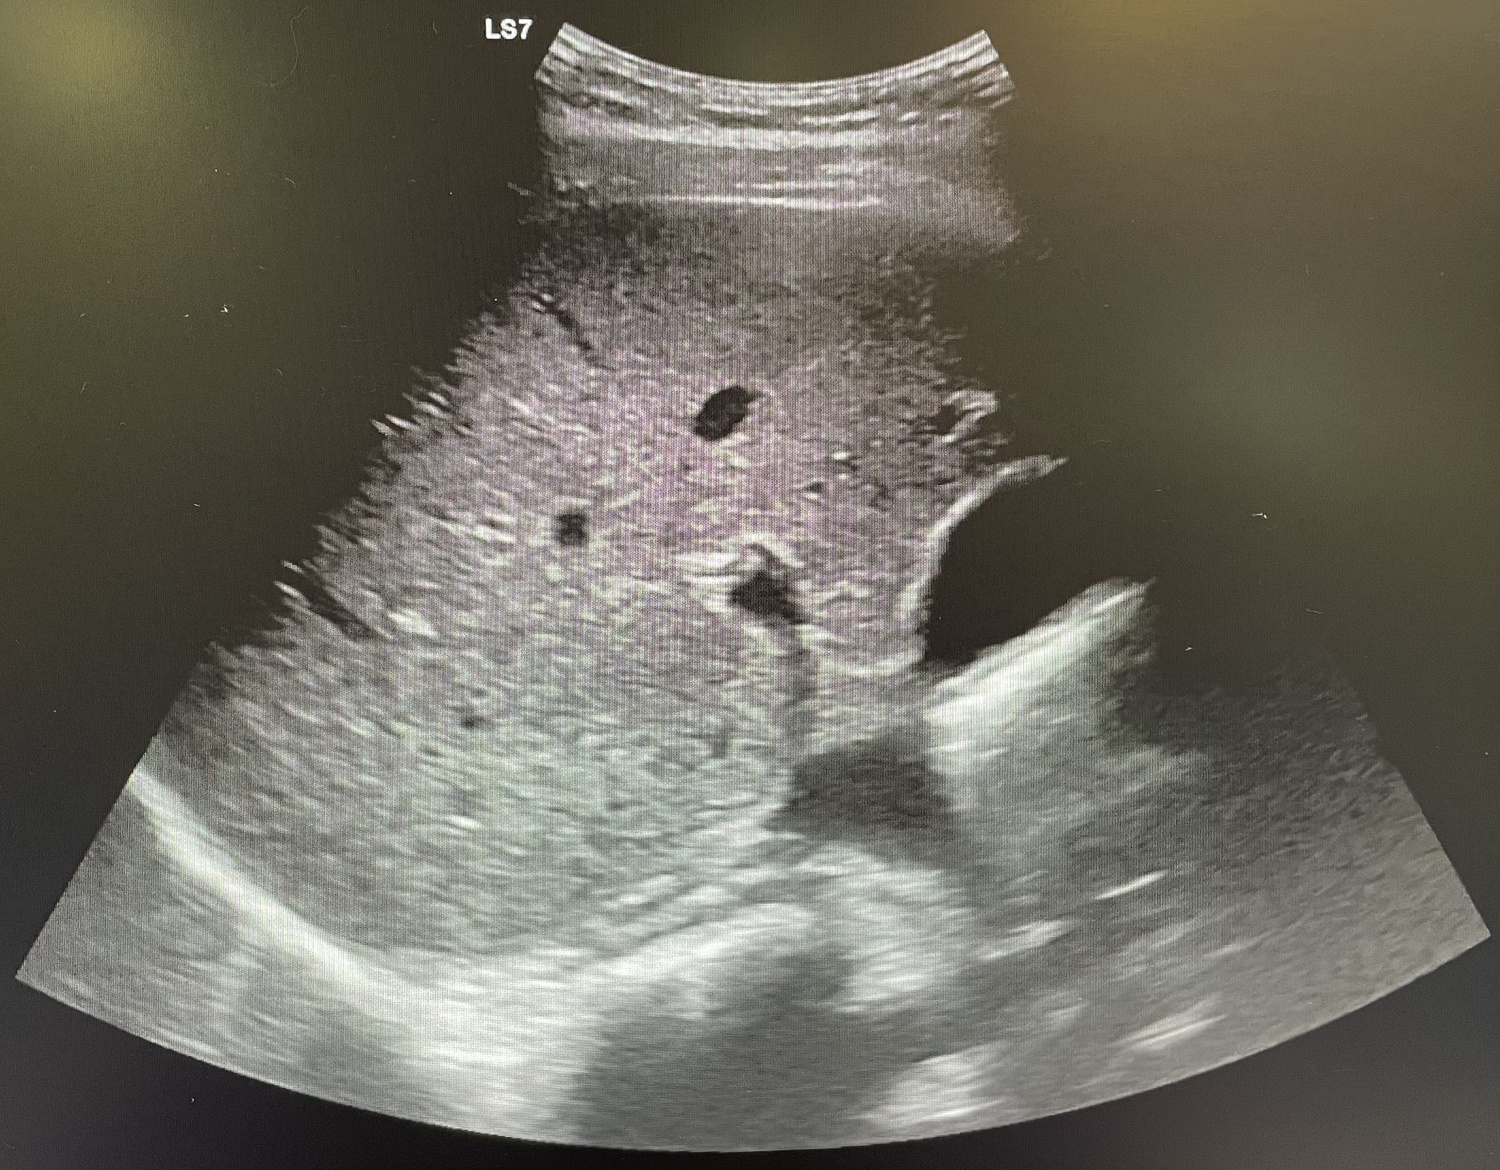

Se realiza analítica con aumento de reactantes de fase aguda (leucocitos 18.00 y PCR 108) y se indica ecografía abdominal que resulta no concluyente, por lo que se procede a alta.

Al día siguiente vuelve con la misma sintomatología, el dolor no cede con analgesia habitual. En la exploración Blumberg claramente positivo, se solicita analítica (leucocitos 13.000 y PCR 127) y se repite ecografía de abdomen que se sigue informando como no concluyente para apendicitis aguda.